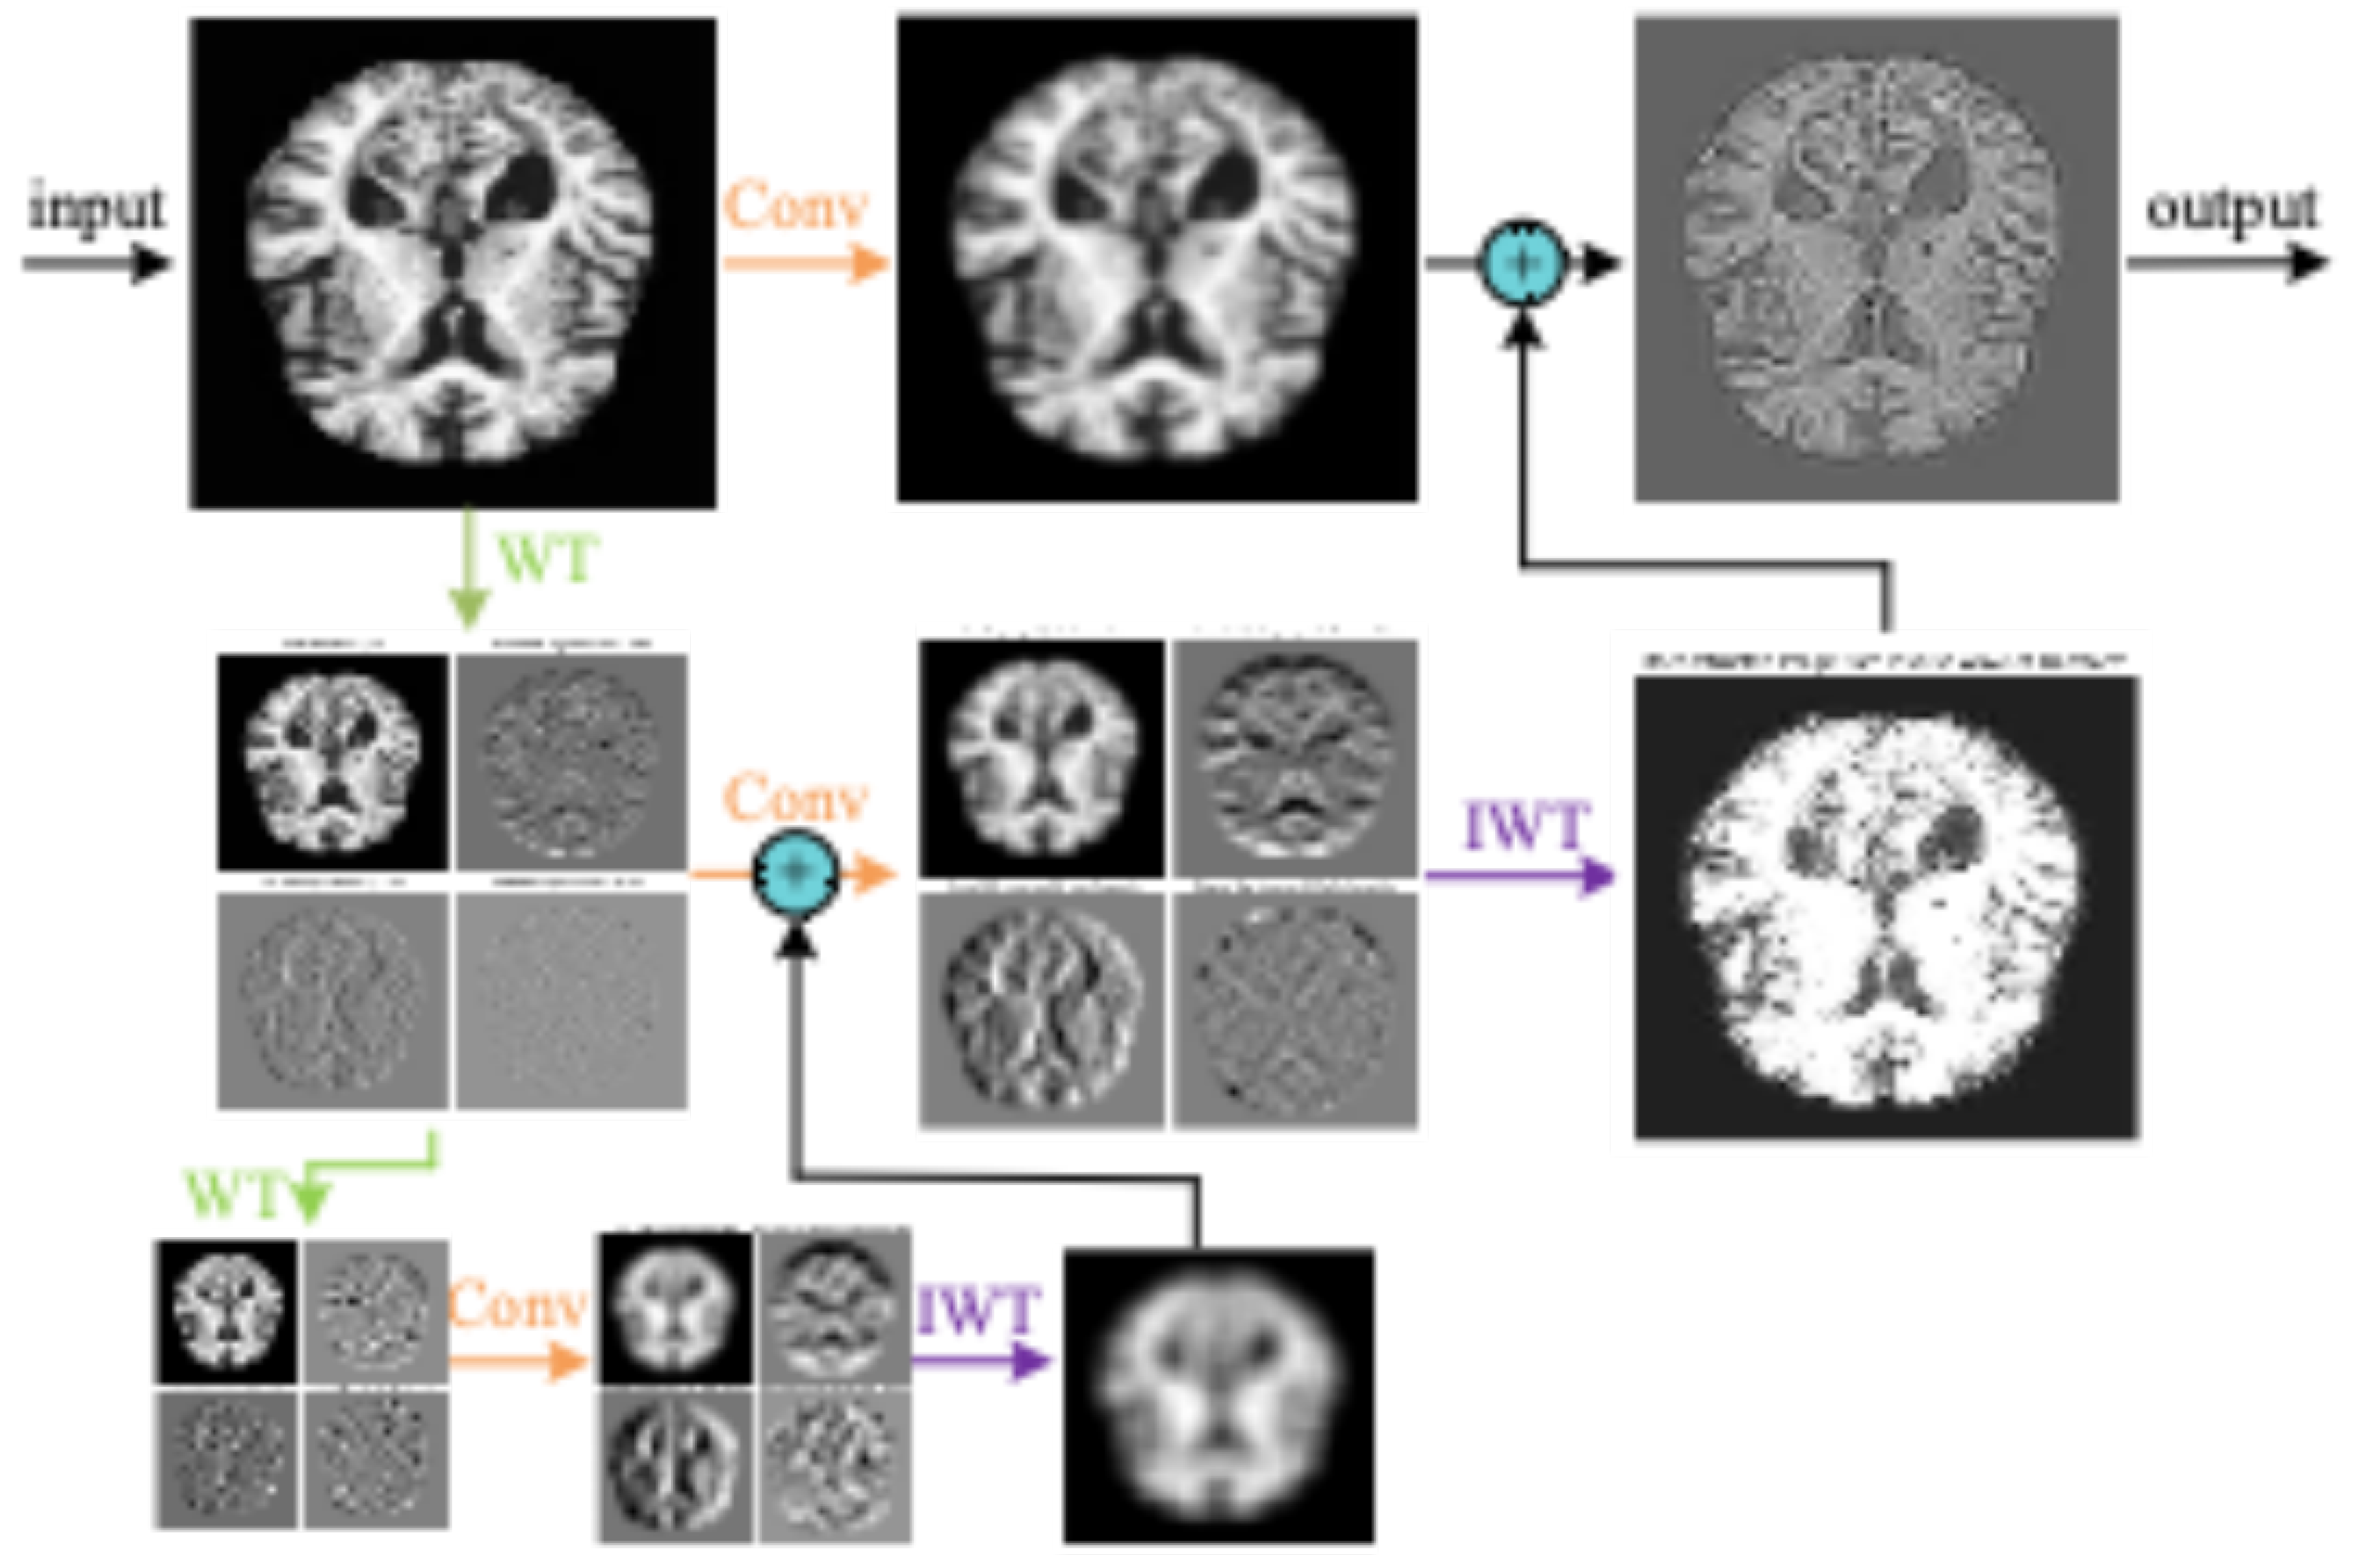

3.1.1. WTRGANet Network Architecture

3.2. Wavelet Transform Convolutional Layer

3.2.5. Feature Reconstruction and Export

- (1)

- The low-frequency component and the high-frequency component are added together to obtain the fused feature map:

- (2)

- The feature maps are reconstructed through the inverse wavelet transform function IWT :

3.2.6. Theoretical Advantages of WTConv2d

- Multi-resolution feature extraction:With the wavelet transform, WTConv2d is able to capture image features at different frequency levels, both extracting local details and preserving global structural information.

- Feel the Wild Expansion:Applying independent small convolutional kernel operations on the high frequency components, WTConv2d effectively extends the receptive field and improves the model’s ability to capture the global information of the image

- (3)

- Parametric efficiency:Using deep convolution, WTConv2d avoids excessive growth in the number of parameters while maintaining efficient feature extraction capability.In concrete terms,Using multi-level wavelet decomposition level WT) The number of parameters increases only linearly as , and the sensory field grows exponentially as . k.